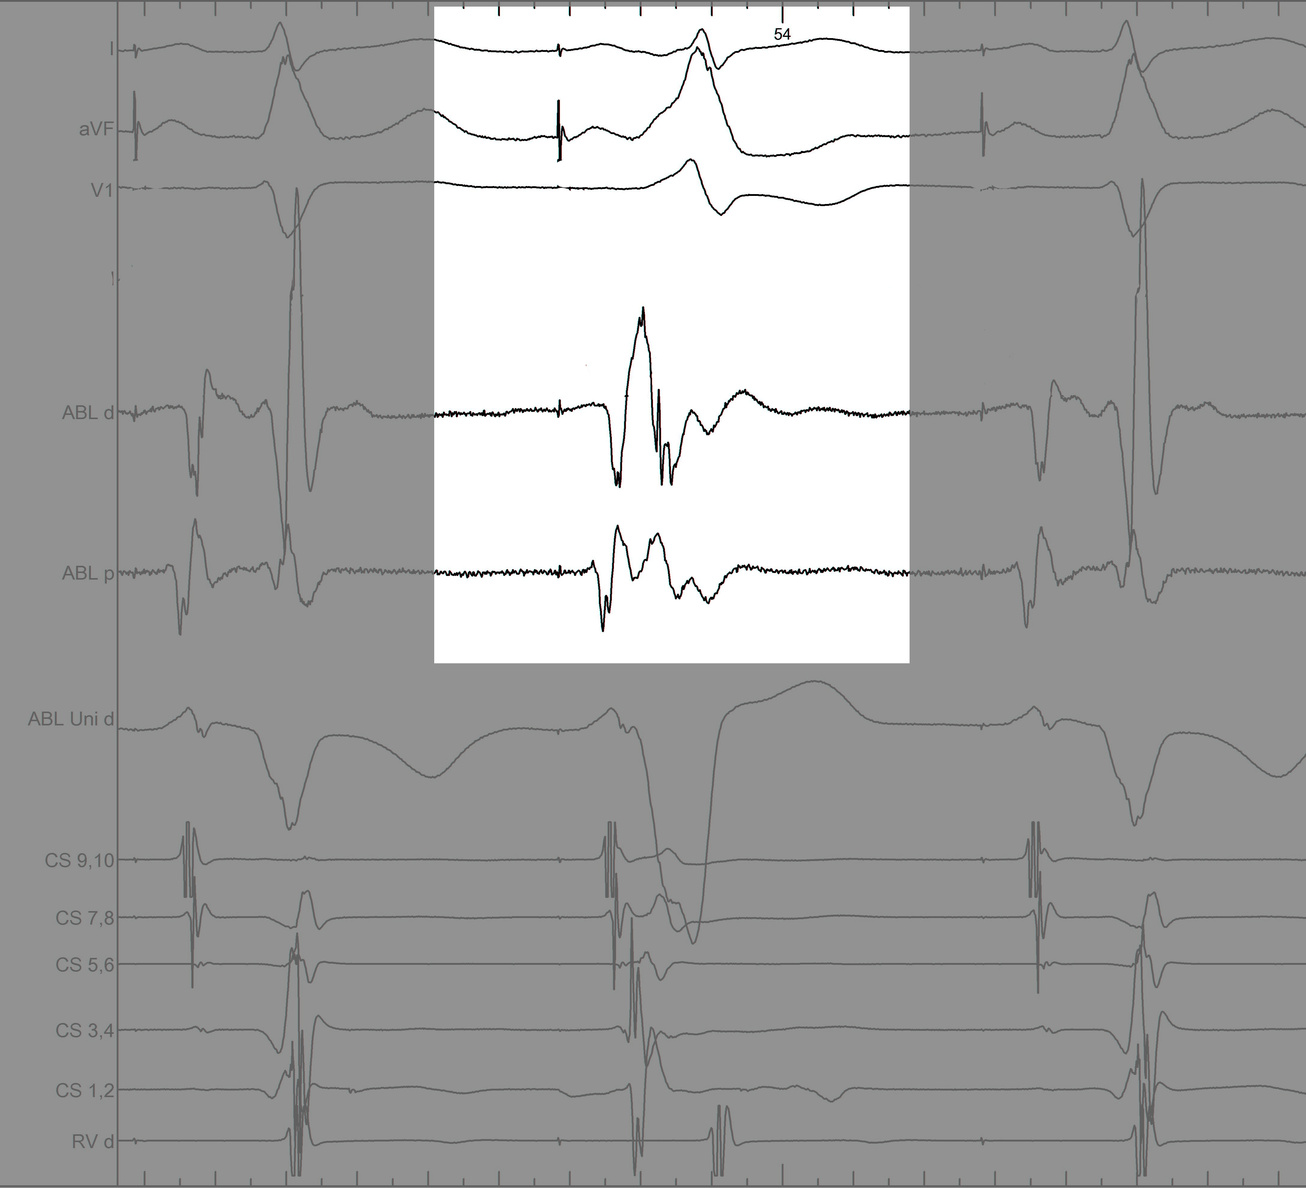

Identify components of the signal

mask2.jpg